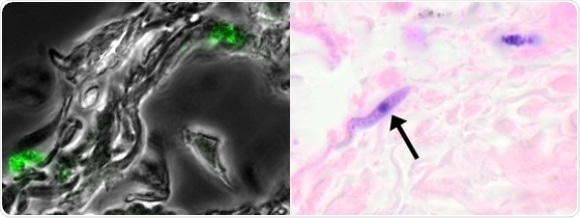

In this study, scientists from the Institut Pasteur decided to monitor the evolution and distribution of Trypanosoma brucei parasites in real time in mouse models. Trypanosomes that had been modified to emit both fluorescence and bioluminescence were transmitted to these mice via tsetse flies, their natural vectors. "We saw a huge number of parasites in the skin, a much larger quantity than in the bloodstream," described Brice Rotureau. "And at tissue level, we observed trypanosomes at the base of the dermis moving in the inter-cellular matrix, outside the vascular system. The parasites were distributed very evenly, as if they were trying to optimize their chances of being taken up by a tsetse fly so that they could be transmitted to a new host."

The study also demonstrated the presence of trypanosomes in the skin of African patients, including individuals who had received a negative diagnosis for the disease. These patients were actually healthy carriers who served as reservoirs for the parasite Trypanosoma brucei gambiense and who should have been treated. All these findings offer new hope for the treatment of sleeping sickness.